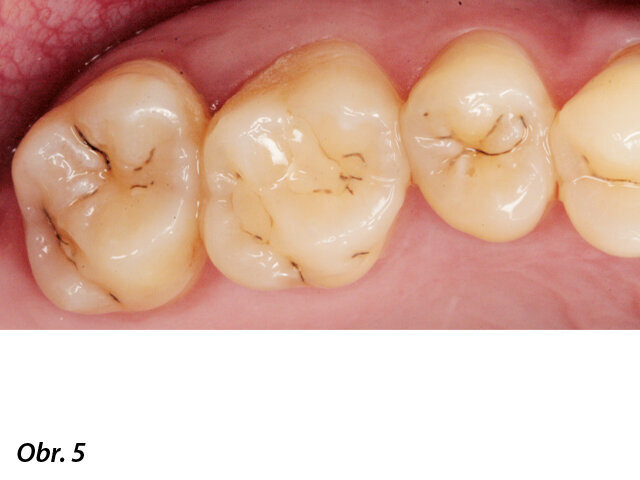

Kazuistika

Pacientka ve věku 38 let přišla do mé ordinace kvůli vyřešení zubních kazů. Při klinickém vyšetření nebyly patrné žádné kazy velkého rozsahu (obr. 1, 2). Až na RTG snímcích typu bitewing (obr. 3, 4), nezbytného prostředku pro diagnostiku v záchovné stomatologii, byly vidět mnohé kariézní léze, které zasahovaly do dentinových tkání. Pacientka požadovala vynikající estetický výsledek, což znamenalo sladění kompozitního materiálu se sklovinnými tkáněmi. Tento požadavek musel být zkombinován s funkční rehabilitací, která by v distálním úseku odolala zatížení žvýkacími silami a zajistila dlouhodobě minimální možné opotřebení. V rámci léčebného plánu bylo pacientce navrženo řešení v podobě přímého ošetření kazů v jednotlivých kvadrantech a nepřímé výplně v zubu 47, které by umožňovalo nejlepší přesnost okrajů a bylo zárukou dlouhodobě vynikajícího výsledku.